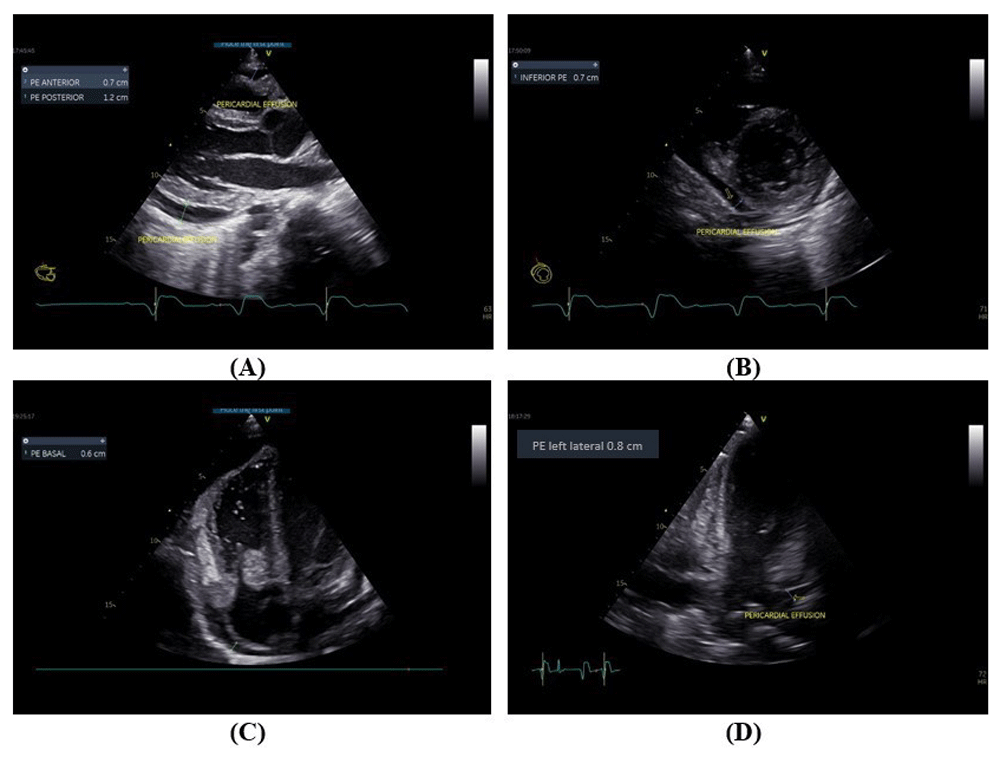

The patient was presented with chest discomfort and general weakness. He was hypotensive and bradycardic with blood pressure of 80/40 mmHg, regular heart rate of 44 beats per minute, respiratory rate of 18 breaths per minute, and oxygen saturation of 97% on room air. Chest auscultation was clear, and no murmurs heard. Electrocardiogram showed CHB with a junctional escape rhythm at 44 bpm (Figure 1). Echocardiography showed normal left ventricle kinetic, normal left ventricular ejection fraction (62%), and normal right ventricle systolic function. There were moderate pericardial effusion and intracardiac masses (2.1 × 0.9 cm and 1.8 × 0.8 cm) in the right atrial and septal leaflet of tricuspid. Hyperechoic areas in the annulus of tricuspid, lateral wall of right atrium and right ventricle, and interventricular septum were also found in an echocardiogram (Figure 2 and Figure 3). Laboratory finding revealed anemia (hemoglobin 8.5 g/dL; normal range 13.3-16.6 g/dL), leukocytosis (white blood count 18,470/mL; normal range 3,370-10,000/mL), hypoalbuminemia (albumin 2.6 g/dL; normal range 3.4-5.0 g/dL), hypokalemia (potassium 3.4 mmol/L; normal range 3.5-5.1 mmol/L), and hypercalcemia (calcium 16.2 mg/dL, corrected calcium 16.9 mg/dL; normal range 8.6-10.3 mg/dL).

Pericardial effusion was found in (A) anterior, posterior, (B) inferior, (C) base, and (D) left-lateral of the heart.

A temporary pacemaker was immediately implanted as the patient showed symptomatic heart block and cardiogenic shock. CHB persisted despite corrected electrolyte imbalance. On the 14th day of admission, the patient developed pleural effusion, and worsening pericardial effusion with echocardiogram showed massive pericardial effusion and sign of tamponade. Further chest X-ray evaluation on the 14th day of treatment (which includes electrolyte imbalance correction, supportive treatment of general weakness condition, anemia, hypoalbuminemia, and infection) showed left parahilar ground glass appearance with suspicions of lung metastasis and pleural effusion (Figure 4). Pericardiocentesis was then performed with pericardial fluid showing hemorrhagic typical for malignant disease.

The presence of right atrial mass in our patient supports the possibility of hematologic spreading of metastatic cancer cells into the endocardium. Pericardial effusion may represent metastasize or inflammatory reaction toward the malignancy. The presence of CHB suggests the infiltration of the heart conduction system.

In our patient, CHB was initially thought to be the result of electrolyte imbalance. However, as the electrolyte was restored to its normal level without any improvement of CHB, it suggested that CHB was caused by infiltration of the metastatic cell to the conduction system of the heart. The presence of hemorrhagic pericardial effusion supports the suggestion of pericardial metastasis. Regardless of the lack of histological confirmation, we suggest that this case was cardiac metastasis diagnosed antemortem.